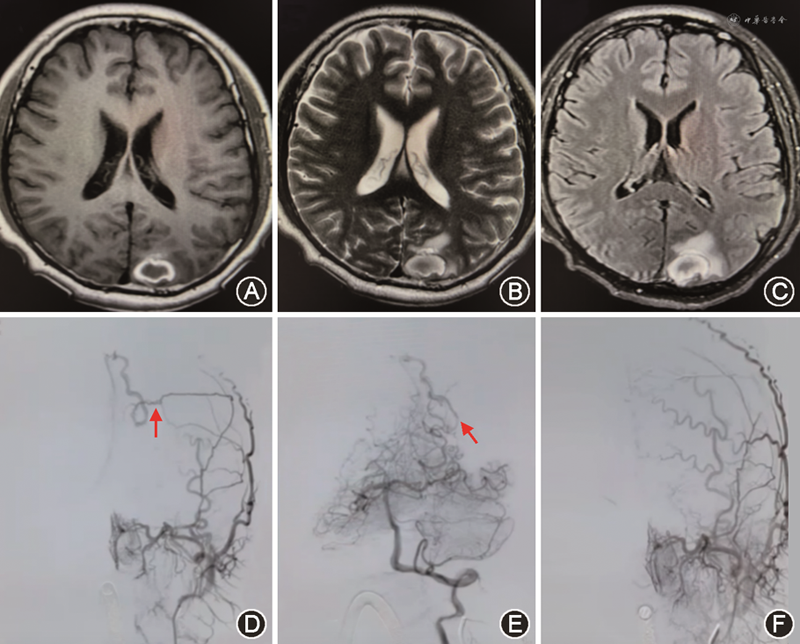

DSA是明确DAVF诊断和分型的“金标准”,可以清楚地显示供血动脉的来源、瘘口的位置、受累的静脉窦有无栓塞及观察静脉回流的方向(图2)。选择性DAVF血管造影应完善6根血管检查:双侧颈内动脉、颈外动脉和椎动脉,如病变位于枕大区者,则加做上颈段血管造影,如双侧甲状颈干造影。DAVF区别于BAVM的特征有如下几点:(1)供血动脉来自颈内动脉、颈外动脉、椎动脉的脑膜支或硬脑膜动脉;(2)无畸形血管团;(3)瘘口位于硬脑膜上而不是脑内。Lang等[23]使用基于人工智能的三维血管造影成像后处理技术,重建脑动脉瘤(10例)、BAVM(10例)和DAVF(10例)的数据影像,发现对血管结构的评估与3D-DSA相当,并大大减少患者的辐射剂量。四维数字减影血管造影(4D-DSA)作为一项新技术,已经引起了人们的关注。Ishikawa等[24]对10例接受了3D-DSA和4D-DSA的检查的DAVF患者进行比较,发现通过3D-DSA获得的MPR图像对供血动脉和瘘口的可见度明显优于通过4D-DSA获得的图像(P<0.05),但诊断准确率差异无统计学意义。

随着介入栓塞材料的发展,血管内介入治疗已成为DAVF的首选治疗方法,可以选择经动脉栓塞或静脉栓塞的途径(图3)。Chen等[28]回顾了415例未破裂的高级别(Borden Ⅱ型或Ⅲ型)DAVF患者,并根据最初的处理方法将其分为4组[保守治疗、栓塞、手术和立体定向放射手术(SRS)],结果表明介入栓塞治疗后完全闭塞率更高,同时减少了DAVF出血及死亡的风险。这些发现支持将介入栓塞作为未破裂的Borden Ⅱ型和Ⅲ型DAVF的一线治疗选择。